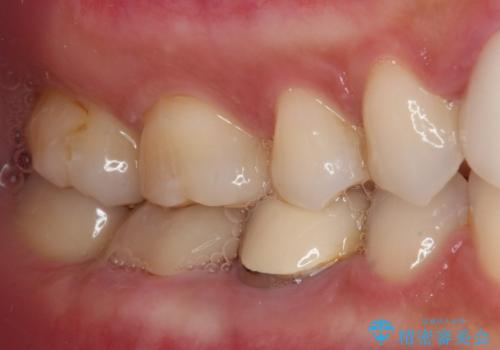

- 他院で治療を開始したものの抜歯が必要と言われ、何とか残せないものかとのことで来院された患者様です。

下顎大臼歯は歯冠部分が残っておらず、保存が難しいように思えましたが、まずは根管治療を行った上で補綴治療を行うこととしました。

上顎臼歯は、おそらく銀歯を外して仮詰めされていたため、再度形を整え、セラミックインレーにて修復治療を行うこととしました。

奥歯は抜歯をせずに保存することができました。ただし、状態は決して良いとは言えないため、定期的に経過を見ていく必要があります。